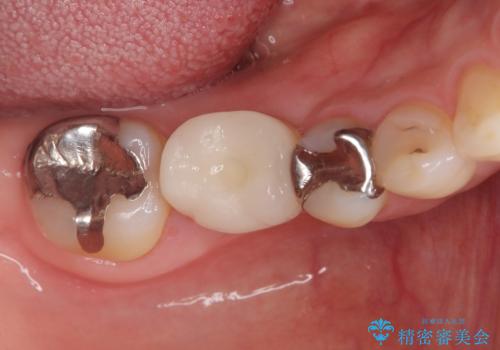

骨の量は十分あったため、比較的短期間で治療は終了しました。

安定した咬み合わせとなり、痛みもなく安心して噛めるようになりました。